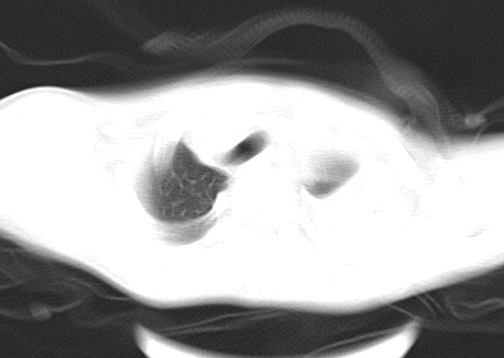

患儿 女 4岁,发热 咳嗽 胸透 考虑:左侧脓胸

左侧胸廓内见大量密实阴影,肺尖部尚有少量肺组织影,纵膈明显受压移位,肋骨未见明显受侵征象,虽然病人年龄较小,但如此大量的“积液”,还是要警惕,不同意一般感染,可结合穿刺脱落细胞学检查。

1)考虑左肺炎症感染。2)左侧大量胸腔积液。

1)考虑左肺炎症感染。2)未经穿刺只能定左侧大量胸腔积液。

左侧张力性大量胸腔积液压迫性肺不张、感染;建议治疗后复查。